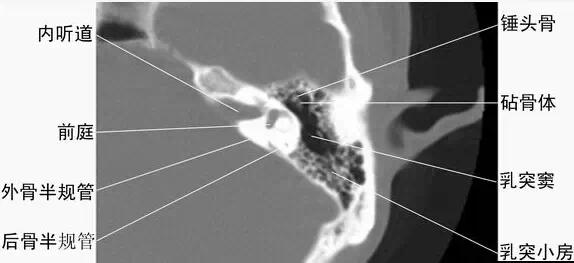

2耳部橫斷面-CT - 解剖圖片